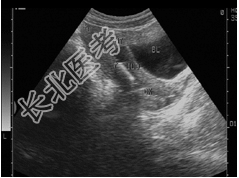

- 单项选择题女性,27岁, 上环3月,月经量多, 超声检查见图,最可能诊断为( )

B、节育器嵌顿

D、节育器下移